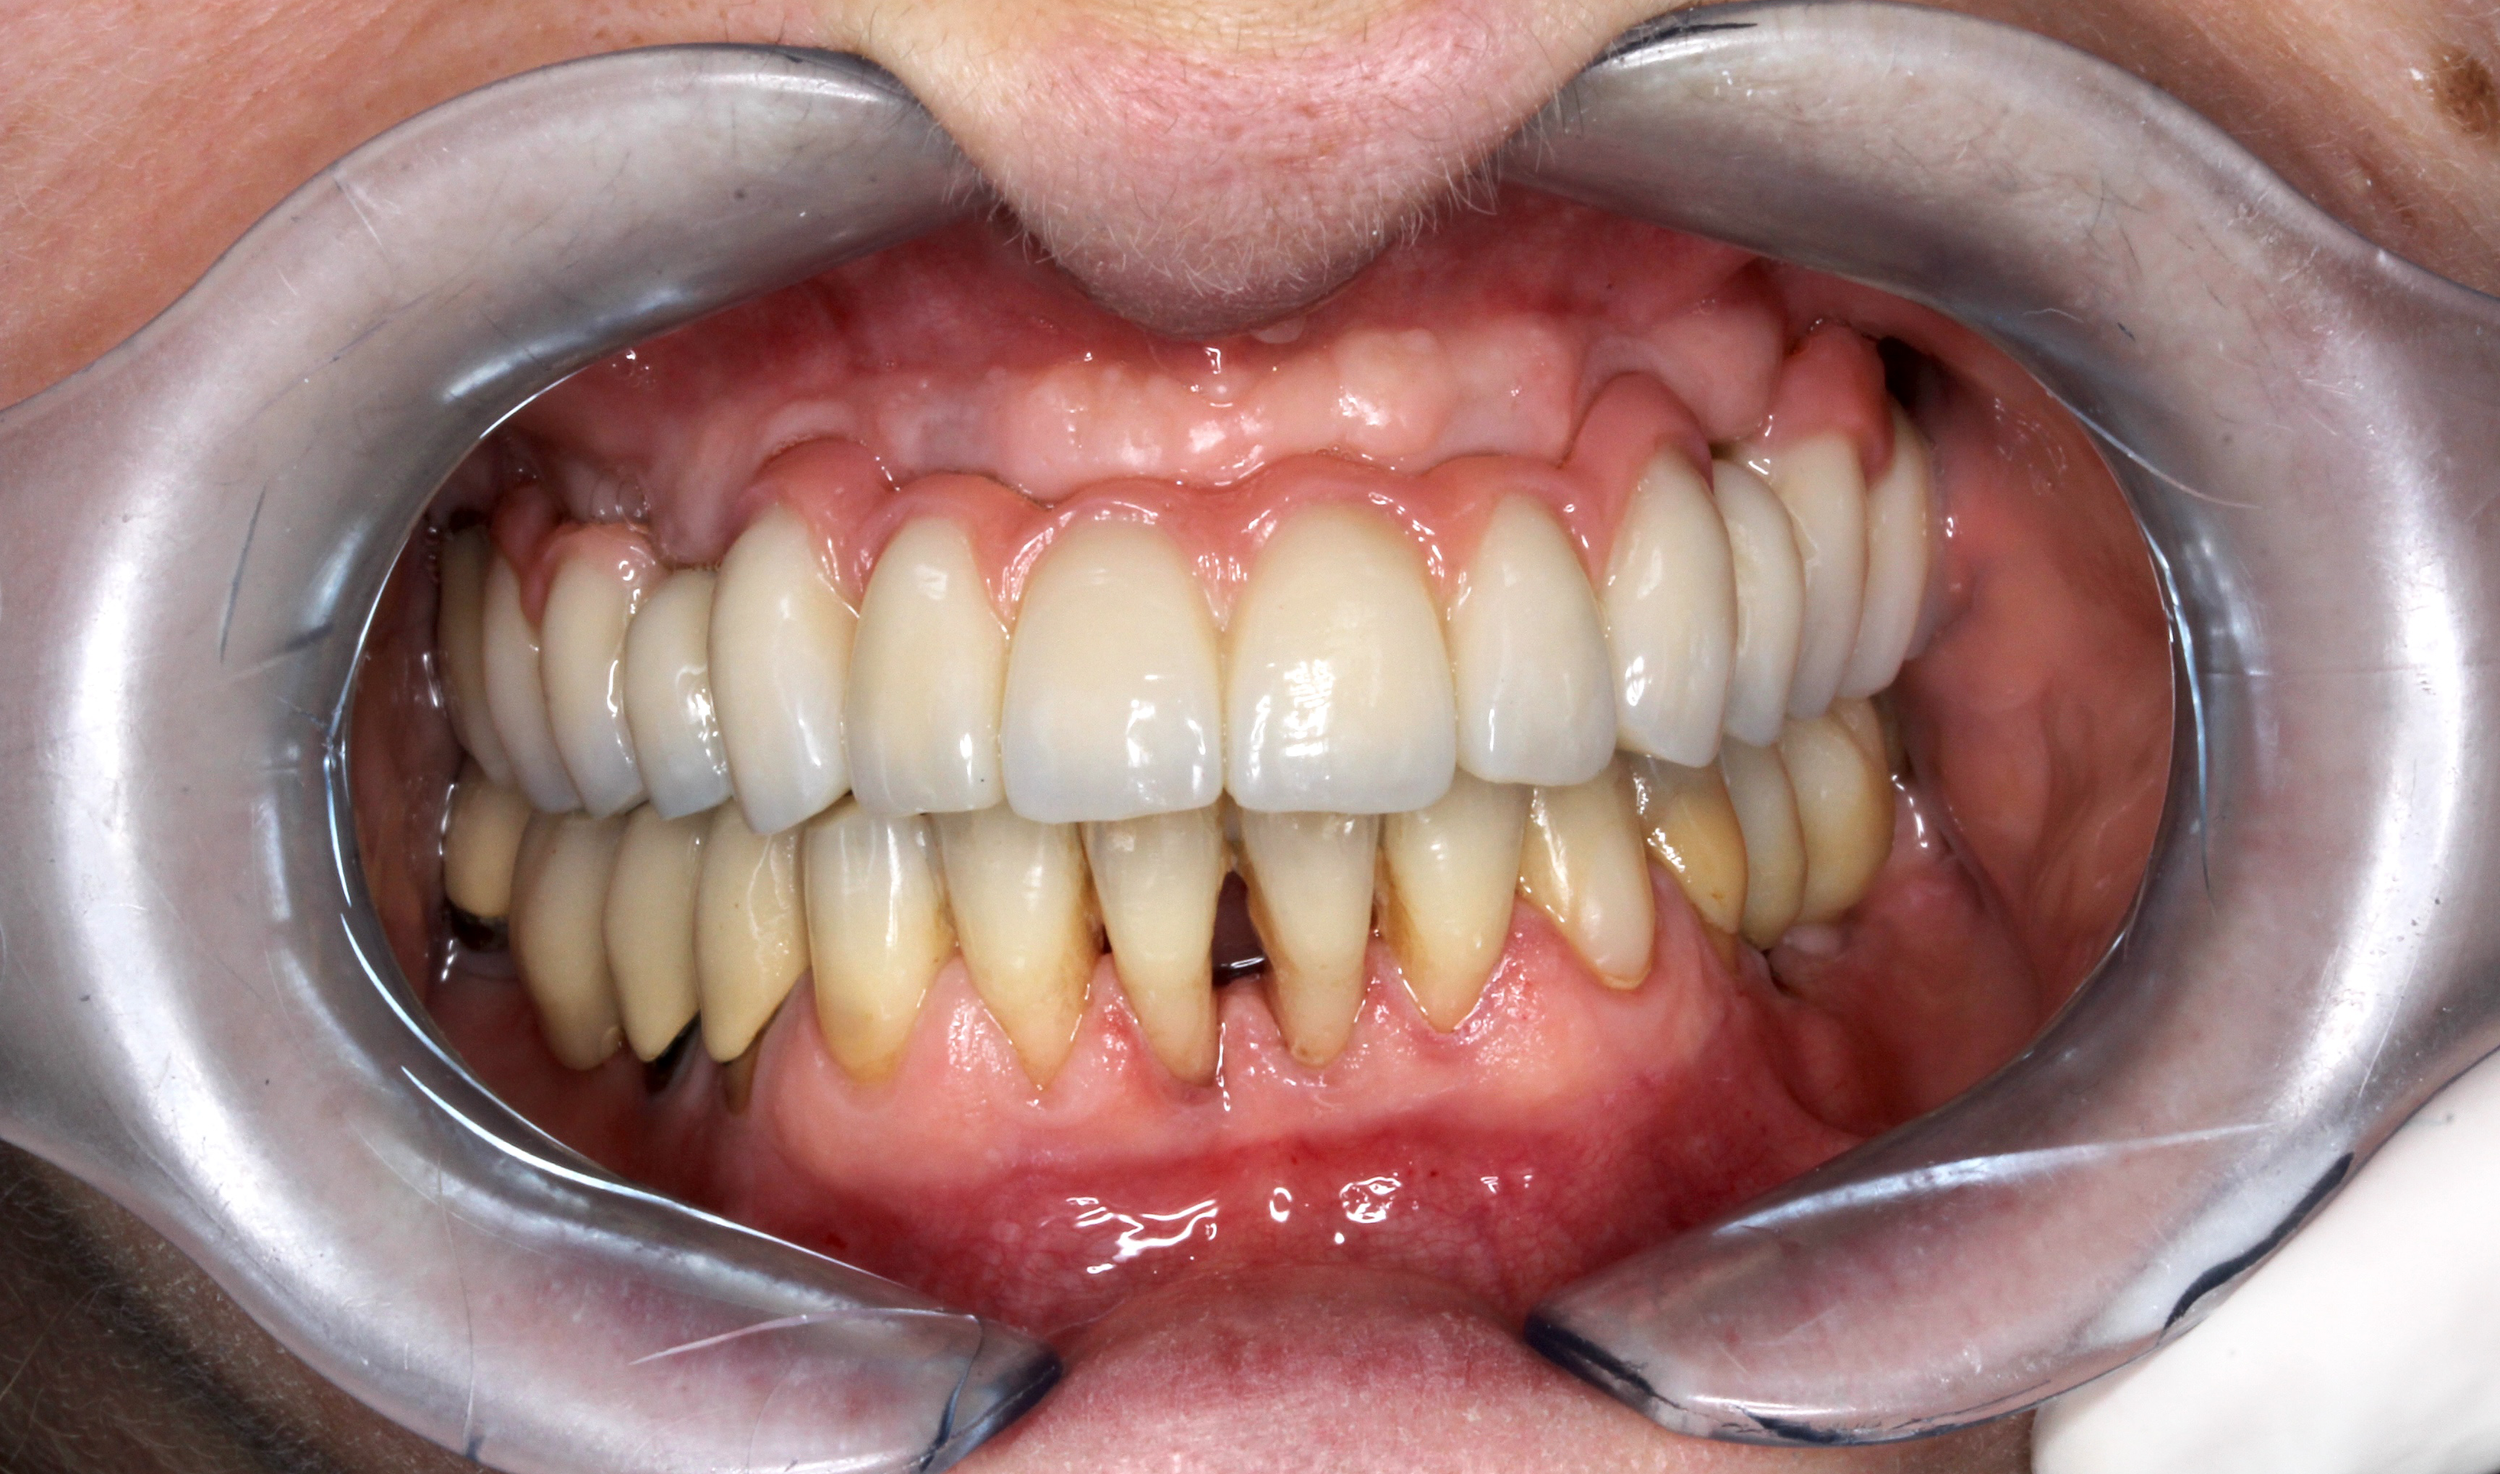

Il paziente, quando era ancora bambino, ha subito un trauma sull’incisivo centrale provocandone la necrosi e interrompendo la crescita completa della radice. Il dente è stato curato e riabilitato in modo tale da mantenerlo in arcata per più tempo possibile. A crescita completa del paziente, a causa dello stato precario dell’elemento dentario, si è proceduto con la sostituzione con un impianto osteointegrato.

PRIMA

DOPO